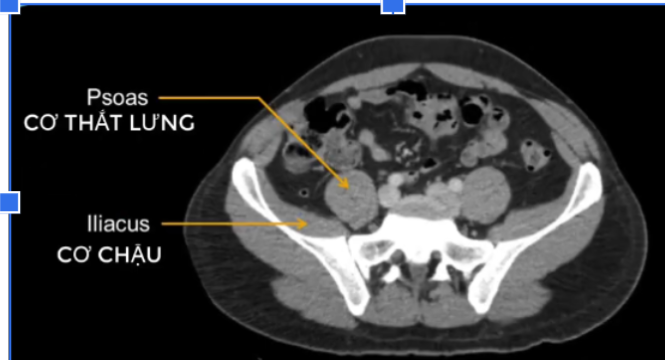

cơ tl? cơ chậu?